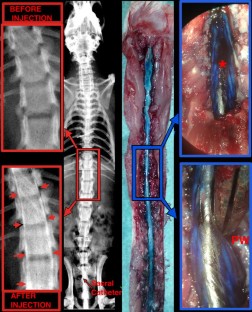

Male Wistar rats had SCI induced at Th10 (n = 7) or a sham operation (n = 10). SCBF was measured using laser-Doppler and CSF pressure via a sacral catheter. Dural integrity was assessed using subdural methylene-blue injection (n = 5) and myelography (n = 5).